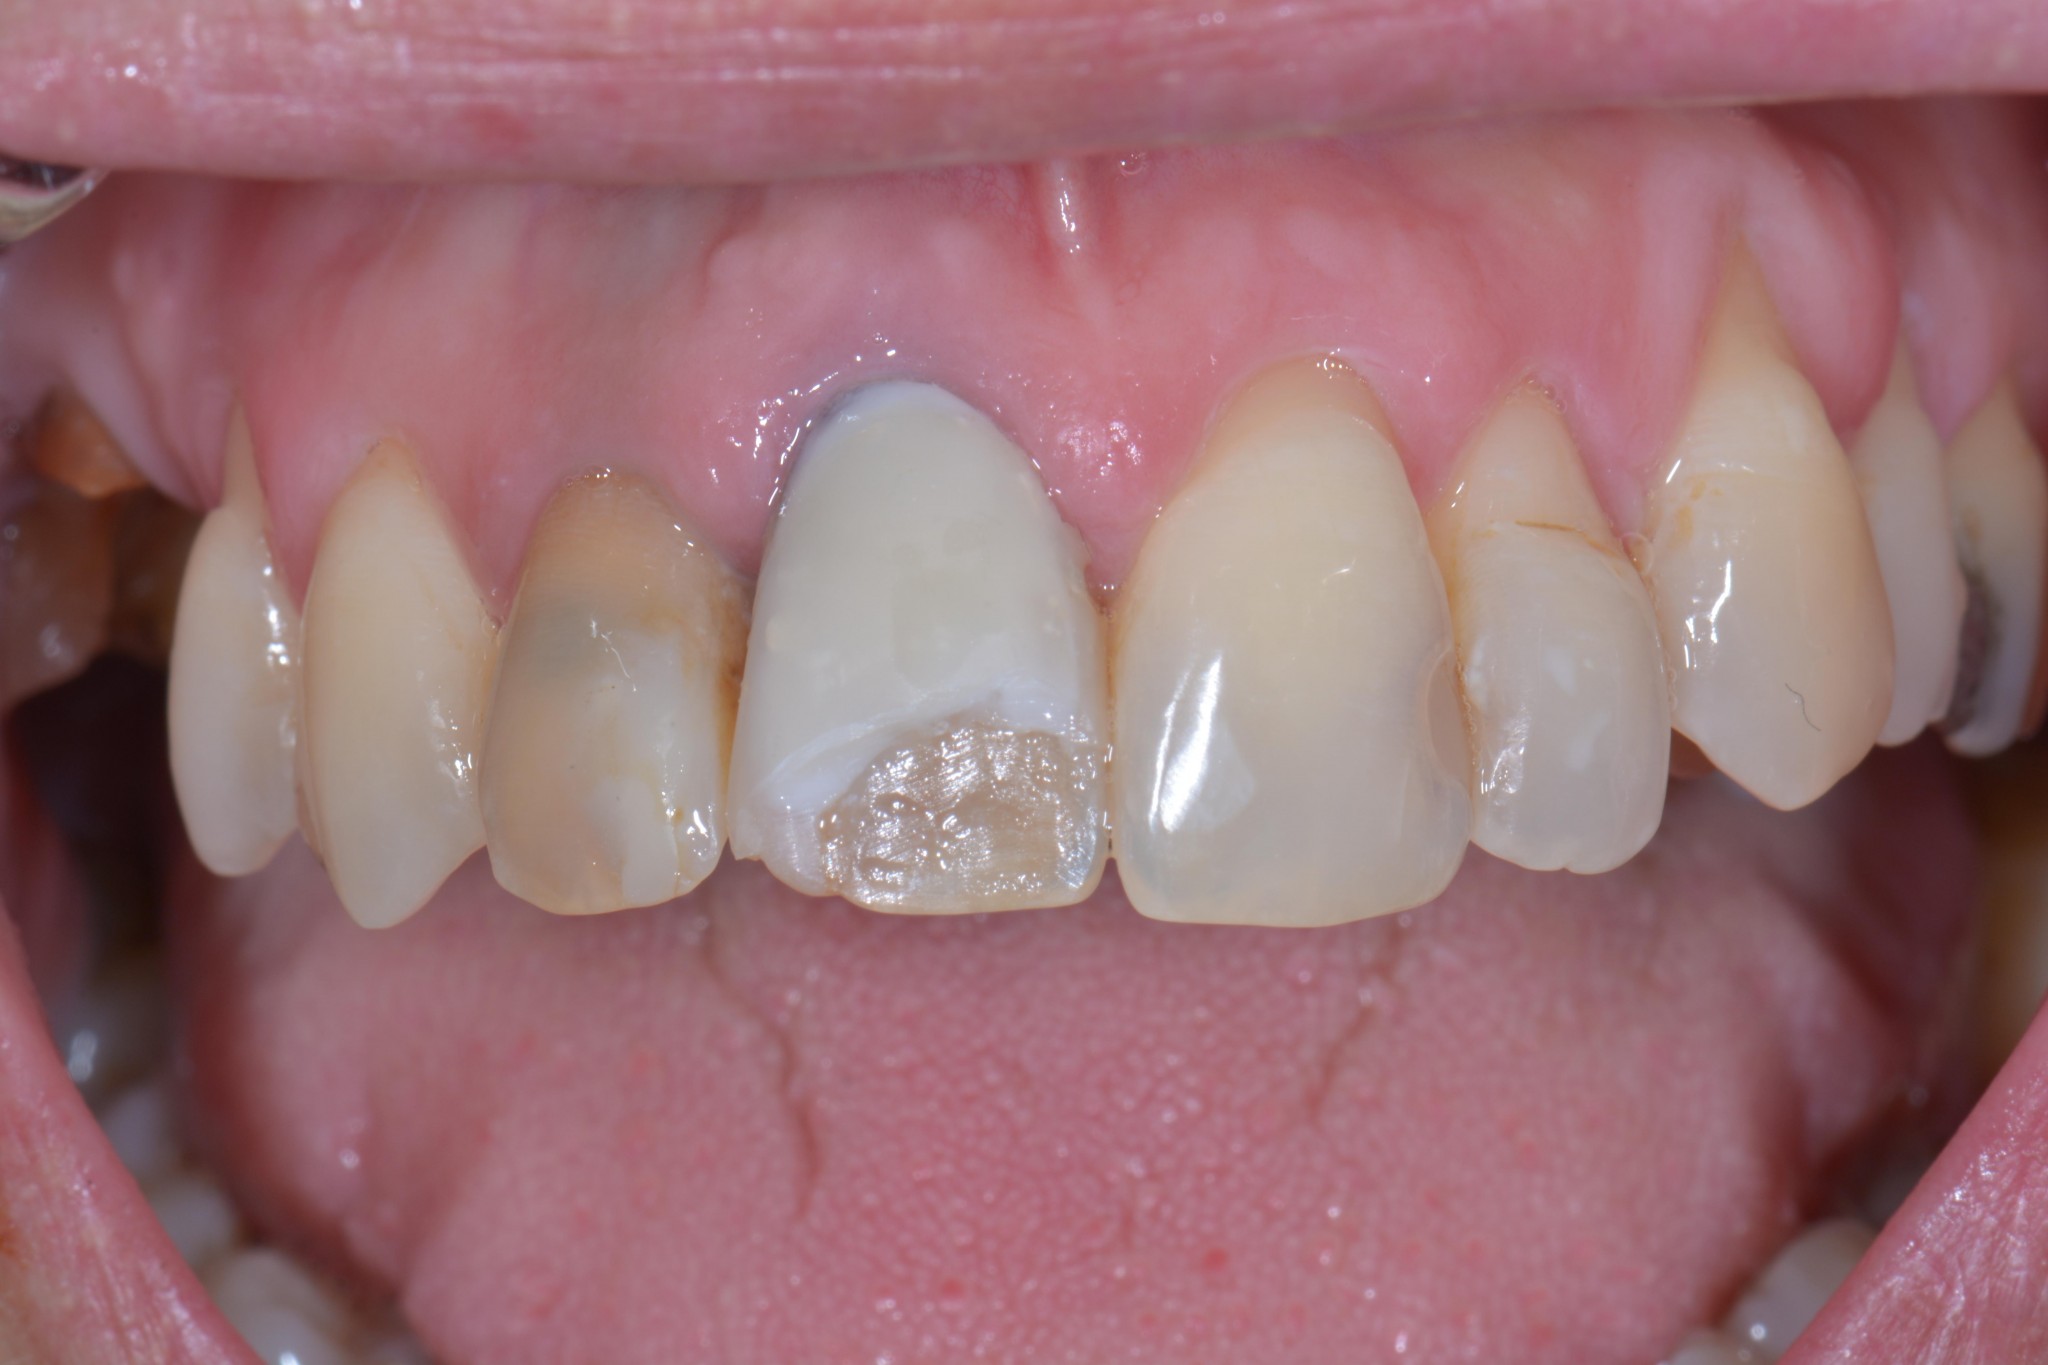

Il dente della signora aveva un perno dentatus a vista dal lato palatino, era discromico, è stato lasciato il vecchio composito sotto la nuova pregiata faccetta, ha il colore sbagliato e andava fissato un appuntamento di revisione per decenza prima di chiedere 250 euro. E poi il 21 ha una carie, il 12 è devitalizzato e deve contenere all’interno una di quelle schifezze di paste di medicazione nere. Il 15 e il 16 anche solo facendo aprire la bocca alla paziente si vede che hanno qualcosa che non va e la paziente mi ha detto “ah, sì, quello mi ha fatto malissimo e il dentista ha detto che la prossima volta vediamo un po’ se si riesce a recuperare, ho già un appuntamento ma a questo punto non vado più e vengo da voi…”